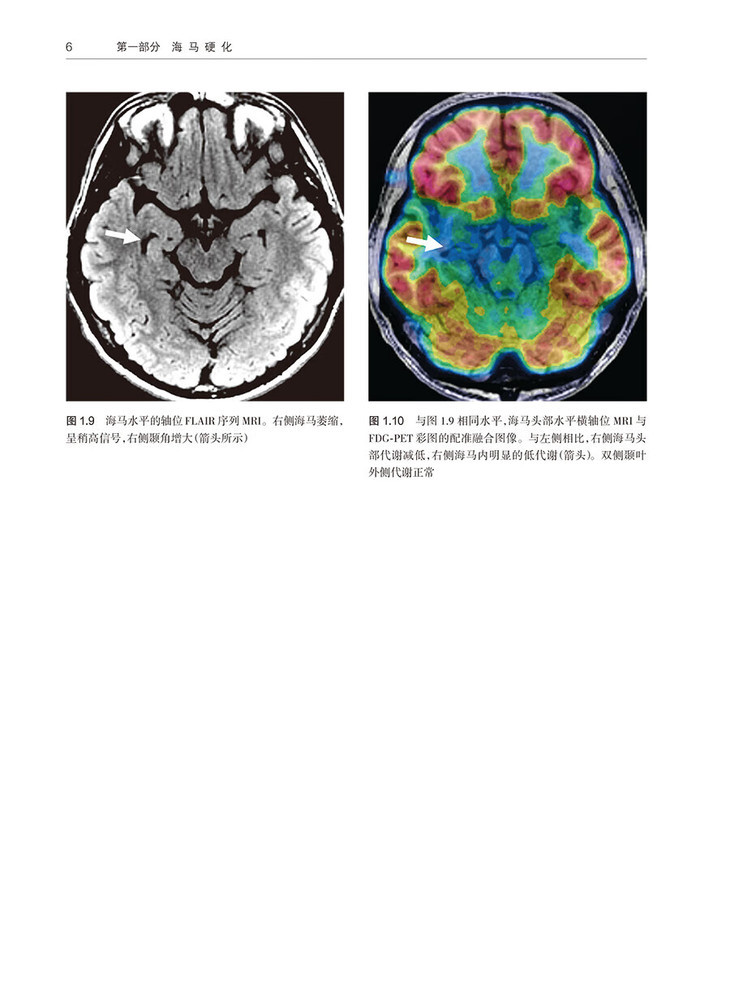

1 轻度单侧海马硬化 /3